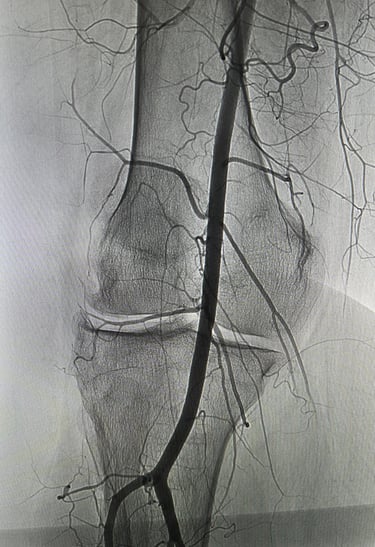

Une artériographie par injection de produit de contraste iodé est réalisée. Elle permet la cartographie des artères à destinée du genou pour repérer les zones d'hypervascularisation et de synovite, qui sont le témoin d'une inflammation locale de la gaine articulaire du genou (la synoviale).

L'objectif de la procédure est de boucher (=emboliser) ces artères anormalement développées qui alimentent les zones inflammatoires de l'articulation, c'est à dire les zones de synovite, pour diminuer l'apport vasculaire et arrêter le cycle de l'inflammation.